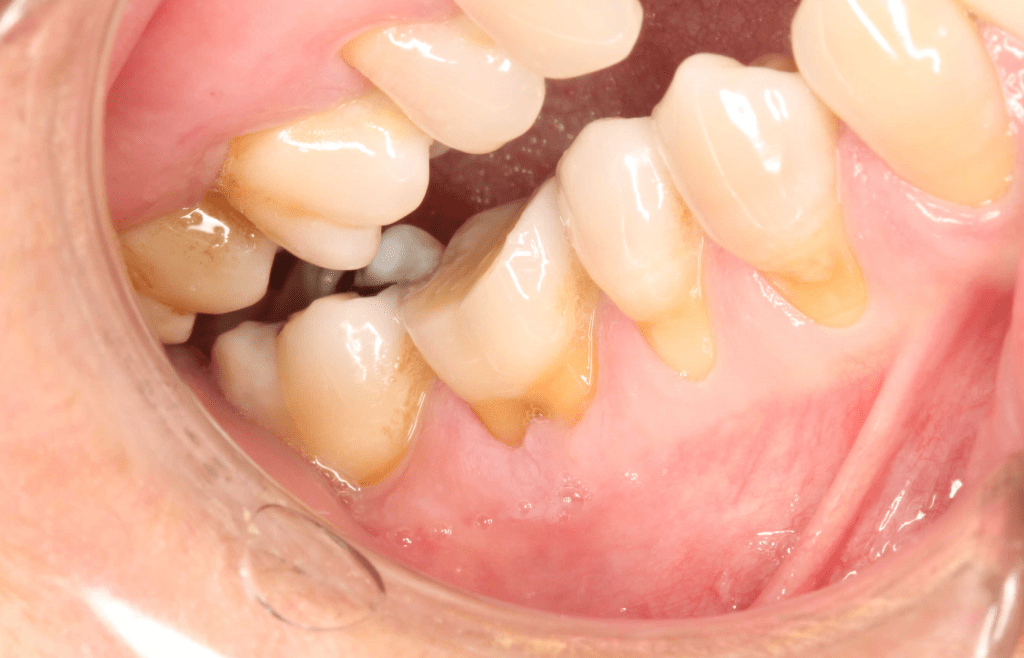

Reco pared vesticular